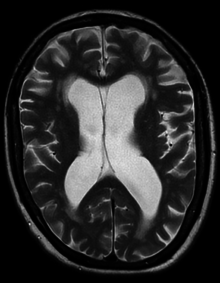

Exceptional case

One exceptional case of hydrocephalus was a man whose brain shrank to a thin sheet of tissue, due to buildup of cerebrospinal fluid in his skull. As a child, the man had a shunt, but it was removed when he was 14. In July 2007, at age 44, he went to a hospital due to mild weakness in his left leg. When doctors learned of the man's medical history, they performed a computed tomography (CT) scan and magnetic resonance imaging (MRI) scan, and were astonished to see "massive enlargement" of the lateral ventricles in the skull. Dr. Lionel Feuillet of Hôpital de la Timone in Marseille said, "The images were most unusual... the brain was virtually absent."[20] Intelligence tests showed the patient had an IQ of 75, below the average score of 100. This would be considered "borderline intellectual functioning", just above what would be officially considered mentally challenged.

The patient was a married father of two children, and worked as a civil servant, leading an at least superficially normal life, despite having enlarged ventricles with a decreased volume of brain tissue. "What I find amazing to this day is how the brain can deal with something which you think should not be compatible with life", commented Dr. Max Muenke, a pediatric brain defect specialist at the National Human Genome Research Institute. "If something happens very slowly over quite some time, maybe over decades, the different parts of the brain take up functions that would normally be done by the part that is pushed to the side."[21][22][23]